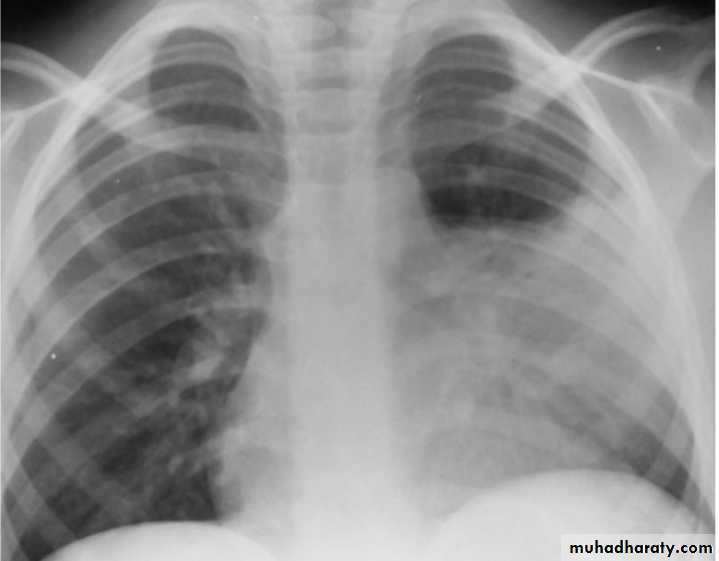

bronchoscopy with bronchoalveolar lavage and brush mucosal biopsy, needle aspiration of the lung, and open lung biopsy are methods of obtaining material for microbiologic diagnosis.Lobar Pneumonia

Bronchopneumonia

CXR:

Frontal & lateral:Bacterial pneumonia characteristically shows lobar consolidation, or a round pneumonia, with pleural effusion in 10% to 30% of cases.

Viral pneumonia characteristically shows diffuse, streaky infiltrates of bronchopneumonia.

Atypical pneumonia, such as with M. pneumoniae and C. pneumoniae, shows increased interstitial markings or bronchopneumonia.